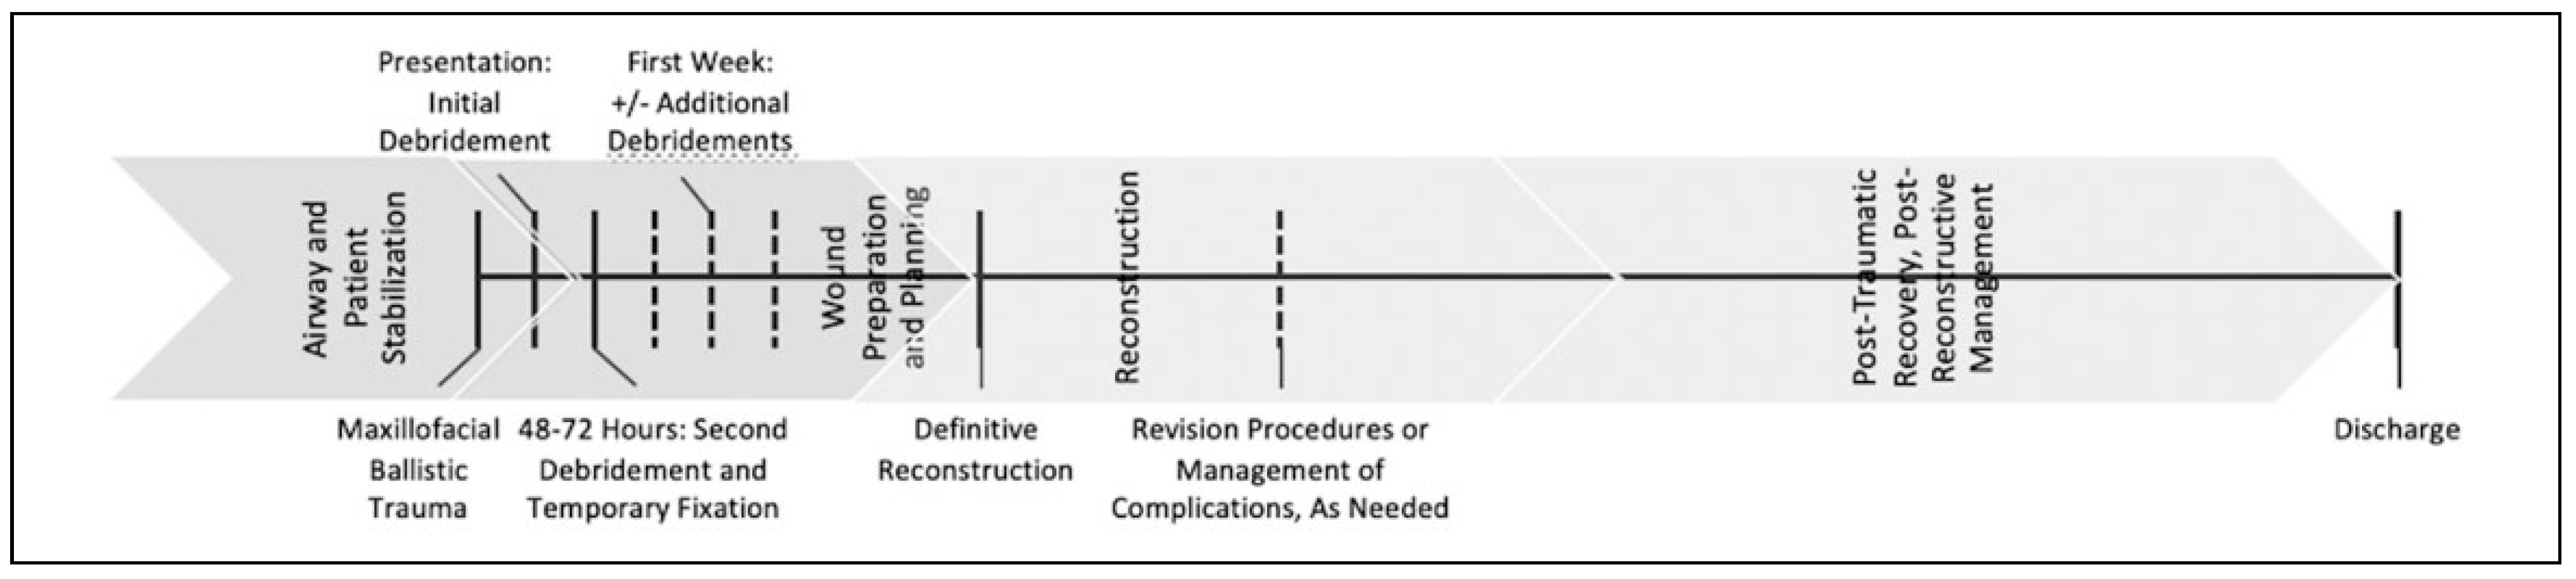

Materials and Methods

Systematic Review

Discussion